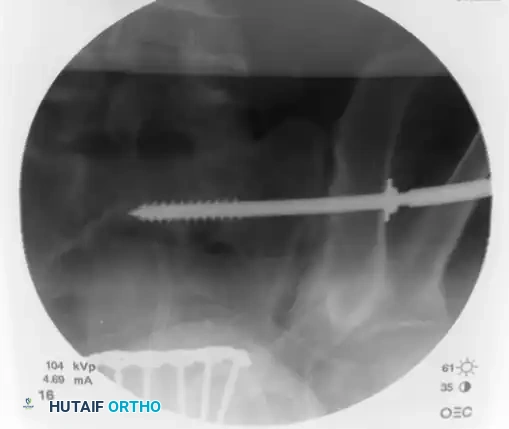

On the lateral fluoroscopic view, place the tip of the guide on the exact predetermined starting spot. Once positioned correctly, impact the guide firmly into the iliac cortex using a mallet. This creates a stable docking point and prevents the guide from skiving along the curved iliac wing.

Remove the inner trocar, leaving the cannulated sleeve docked in the bone. Insert a threaded 2.8 mm or 3.2 mm guidewire into the sleeve.

Image

Utilizing biplanar fluoroscopic imagery—rapidly alternating between the inlet and outlet views—adjust the trajectory of the guide sleeve to safely target the center of the S1 vertebral body.

• On the Inlet View: Aim for the center of the sacral body, staying well posterior to the anterior sacral cortex and anterior to the spinal canal.

• On the Outlet View: Aim between the S1 superior endplate and the S1 neuroforamen.